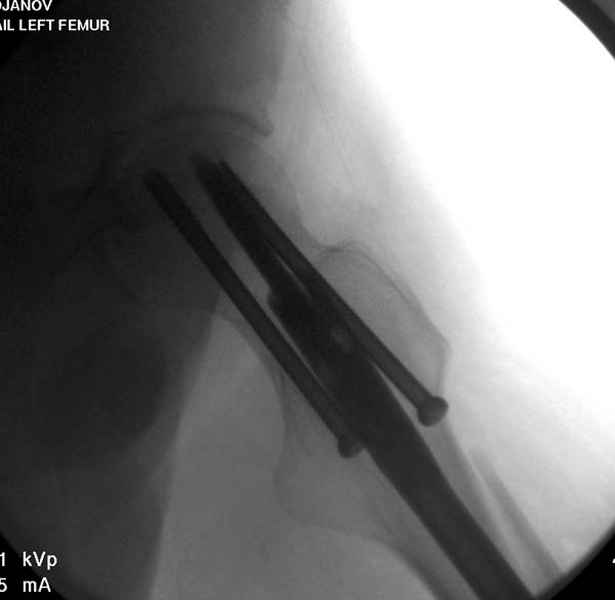

Учитывая, что случай ургентный, больной поступил вечером, не стали делать вытяжение и срочно провели операцию по фиксации перелома бедра антеградным штифтом Versa Nail от DePuy.

Для профилактики дальнейшего раскола в шейке предварительно во время проксимального рассверливания спереди и сзади провели временные спицы, которые в дальнейшем были заменены на шурупы (miss nail method)